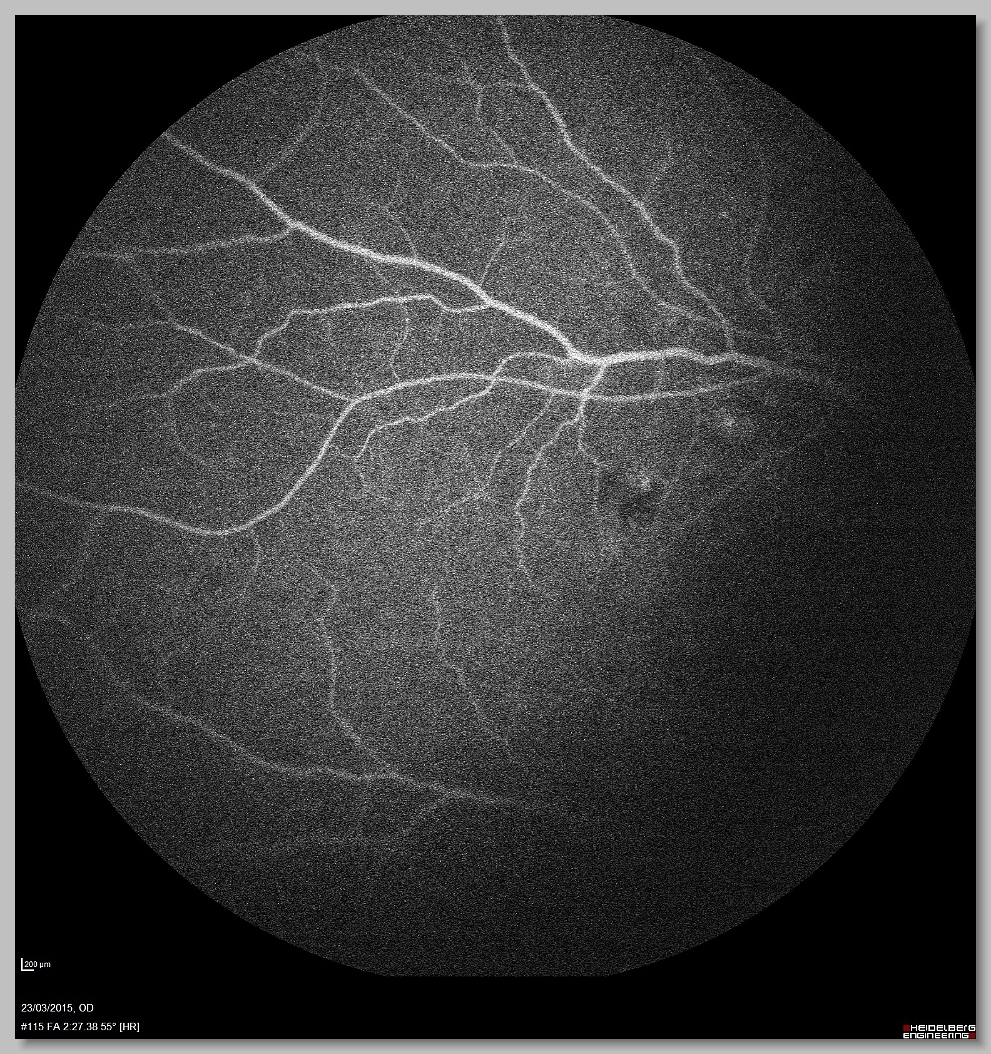

FA 000 FA 001 FA 002 FA 003

FA 004 FA 005 FA 006 FA 007